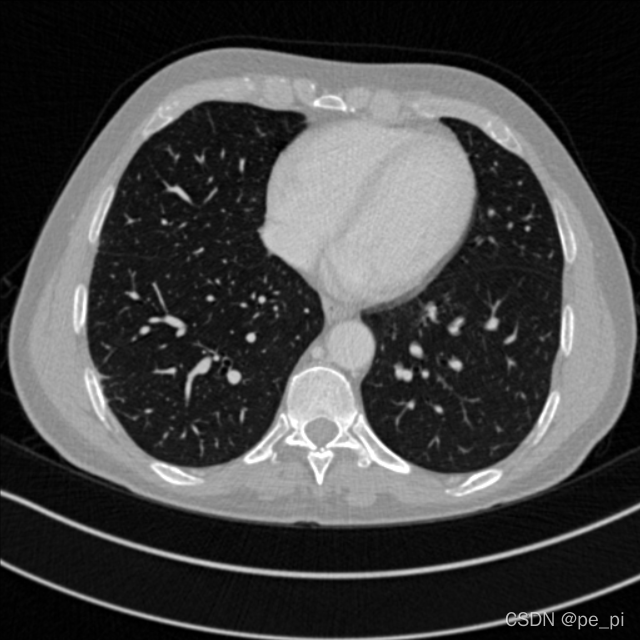

return Hu(2)获得HU为单位的图像的矩阵后,需要针对HU图像进行调窗,以适应于我们对不同部位的图像进行分析(医学图像中不同部位的适用的HU范围不同,这个范围叫做窗口),在imageJ中窗口的大小叫做window,窗口的中心叫做level,在这几个参考的帖子中有不同的叫法,在此按照ImageJ 的名称[5,6]。

return norm_调窗后的数据就是想要查看的数据范围了,在这里对不同部位调窗的数据值设定也不相同[7].